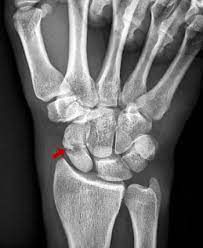

What causes scaphoid fractures

Any impact to your wrist can cause scaphoid fractures. The most common causes include: Falls: Catching yourself with outstretched arms. Sports injuries. Car accidents.